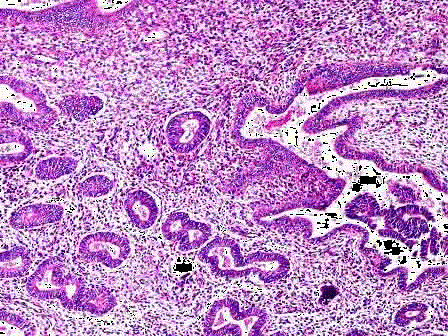

问题 女性,46岁,阴道不规则出血1年,诊刮子宫内膜,显微镜下见腺体增生密集,与间质比>3:1,腺体呈乳头状,可见背靠背现象,伴嗜酸性粒细胞浸润,腺上皮异型性并见核仁(如图),应诊断为 ( )

选项 A.子宫内膜单纯性增生 B.子宫内膜复杂性增生 C.子宫内膜单纯性增生伴非典型增生 D.子宫内膜复杂性增生伴非典型增生 E.子宫内膜腺癌